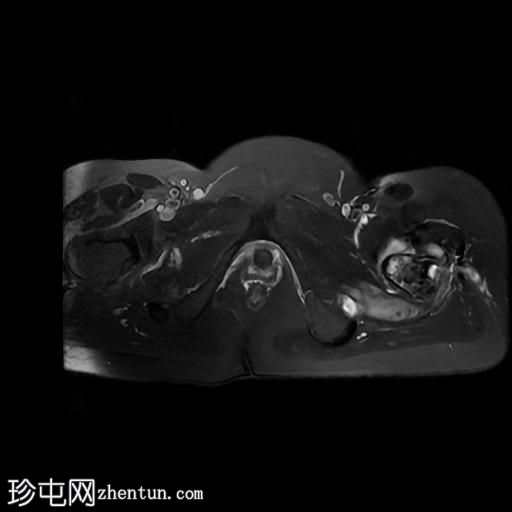

轴位

T2加权像

轴位T2加权像

左髋关节存在严重的关节病变,表现为关节间隙显著变窄、软骨丢失、软骨下骨髓水肿以及囊性改变。

此外,左股骨颈基底部、股骨粗隆间区及股骨大转子区域可见骨髓信号异常及皮质破坏。伴有滑膜增厚及较大的冷脓肿腔,提示左股骨颈及股骨粗隆间区骨髓炎。

另一处较大的冷脓肿从股骨受损部位开始向上延伸至左侧臀肌。

在左侧股骨外侧皮下可见低信号窦道。